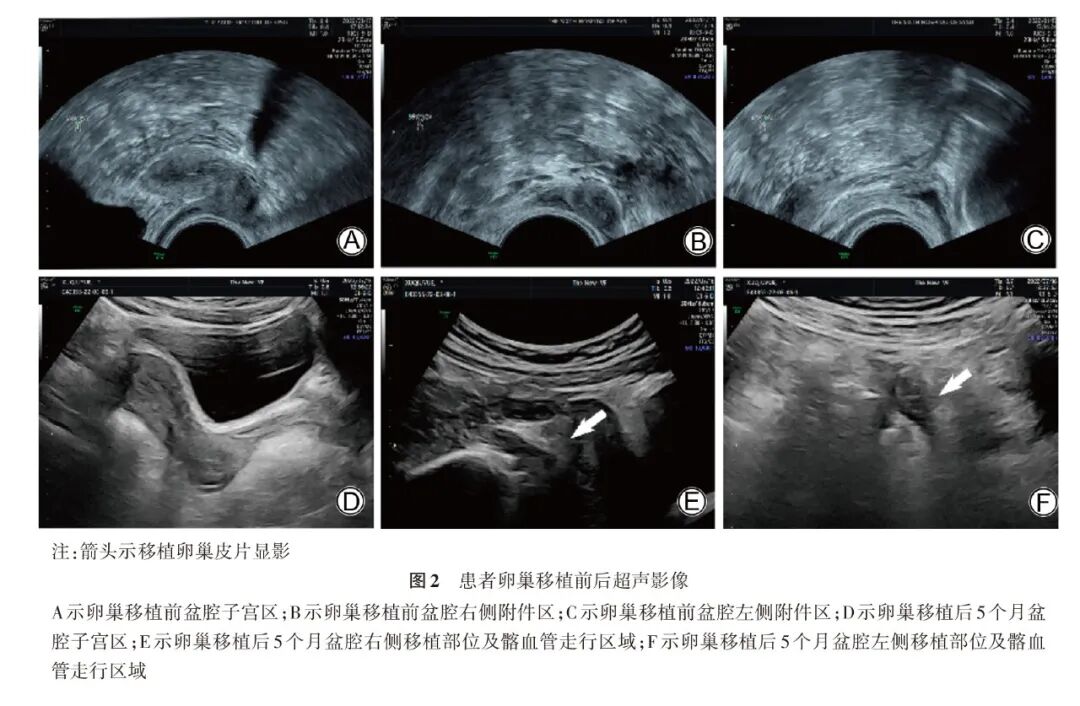

4.随访:卵巢移植术后定期随访患者性激素及盆腔超声改变,患者卵巢组织移植前性激素提示卵巢衰竭。2022年6月26日(移植后第5个月)患者性激素:AMH水平为0.02 μg/L,FSH水平为14.42 U/L, LH水平为6.79 U/L,雌二醇水平为134.2 ng/L,孕酮水平为1.31 μg/L。患者于2022年6月27日出现阴道出血。2022年7月7日患者性激素:AMH水平为0.02 μg/L,FSH水平为9.71 U/L,LH水平为2.47 U/L,雌二醇水平51.1 ng/L,孕酮水平为0.05 μg/L。提示卵巢组织移植成活,生殖内分泌功能开始恢复(激素变化如图1)。2021年7月16日患者卵巢移植术后盆腔彩色超声显示:卵巢移植后患者子宫增大,宫体大小约41 mm×25 mm×23 mm,子宫内膜厚度6.3 mm,盆腔双侧移植部位探及卵巢组织样回声,左侧卵巢组织移植部位探及2~3个直径2~3 mm窦卵泡声像(详见图2A~2F)。